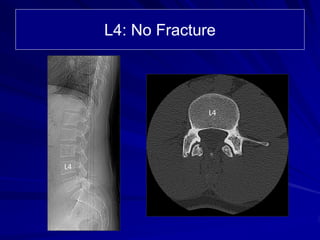

The document details the case of a 25-year-old major league baseball player diagnosed with multiple pars and pedicle fractures in the lumbar spine after experiencing back pain due to pitching. Conservative treatments failed, leading to a proposed surgical strategy involving laminotomy, spinal fixation, and fusion to address the fractures and alleviate nerve root entrapment. The player has additional comorbidities and underwent thorough imaging to guide the surgical approach.